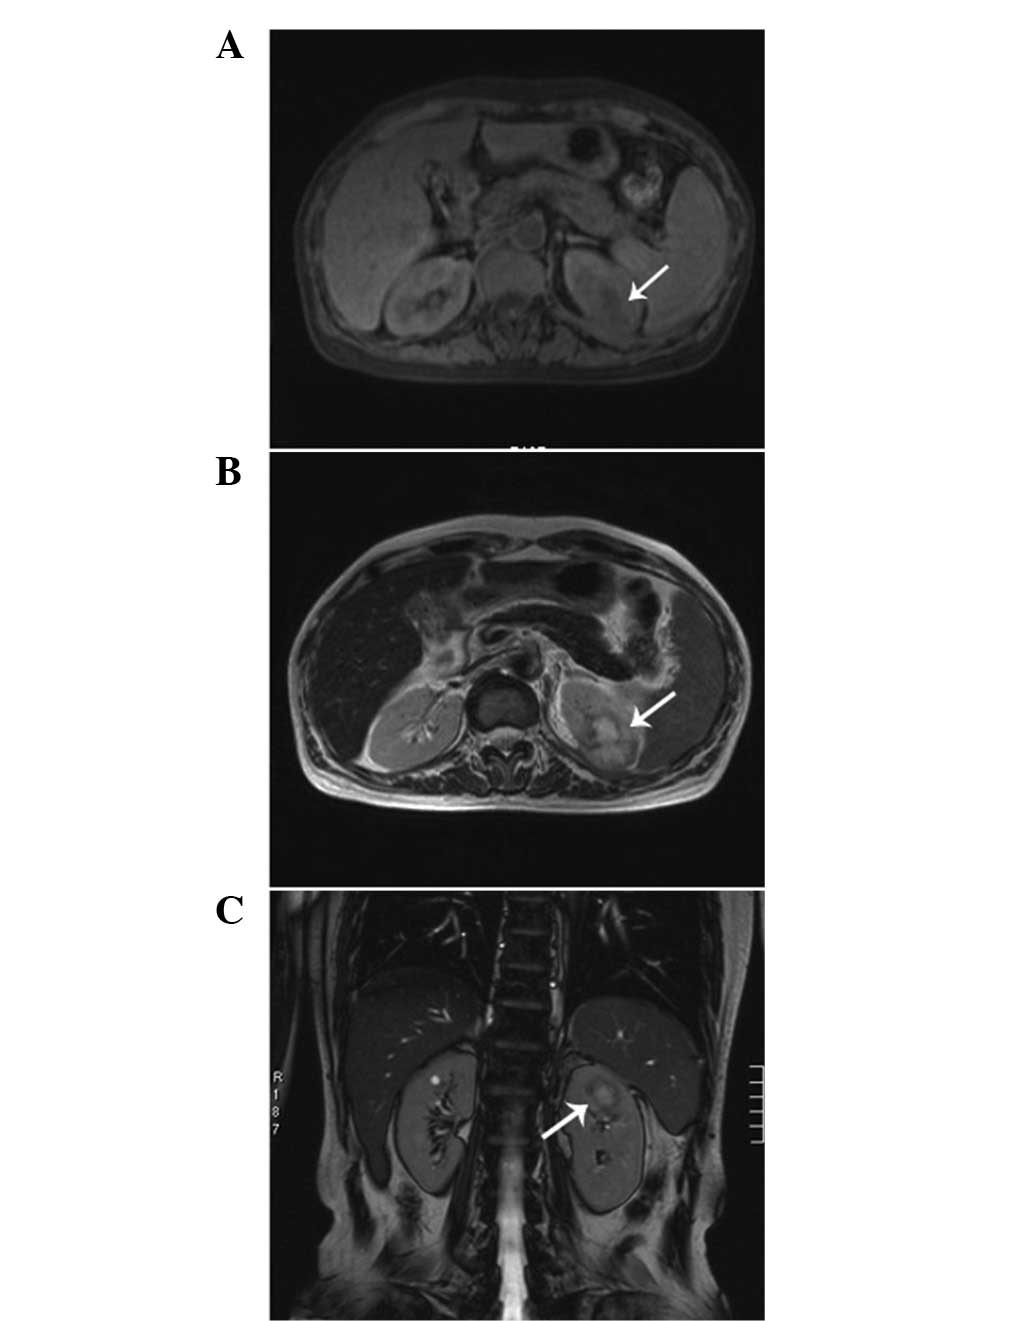

A 48-year-old female visited the First Hospital, Jilin University (Jilin, China) for routine check-up for hepatitis B on July 19, 2012 and presented with no symptoms. The patient had a history of trauma to the left hypochondrium 13 years previously and a history of hepatitis B for 20 years. The latter developed into hepatic cirrhosis, hypersplenism and coagulation disorders. The physical and basic paraclinical examinations were normal. Blood tests revealed a leukocyte count of 2850/mm3, a hemoglobin count of 5.6 g/dl, a platelet count of 6700/mm3, a urine leukocyte count of 20.1/HPF and a urine erythrocyte count of 2.5/HPF. The thrombin time was 19.4 sec and the prothrombin time was 14.0 sec. The international normalized ratio was 1.21, the prothrombin ratio was 1.22 and the prothrombin activity was 69%. Clinical laboratory measurments revealed the following levels: Serum fibrinogen, 0.55 g/l; hepatitis B virus surface antigen (HBsAg), 197.260 IU/Ml; hepatitis B virus e antigen, 0.299S/CO; hepatitis B virus e antibody, 0.110S/CO; and hepatitis B virus core antibody, 18.210S/CO. An abdominal ultrasonography revealed a 1.4×1.4-cm-sized mass with an obscure boundary in the upper pole of the kidney, which protruded through the surface. The computed tomography (CT) scan revealed a 1.6×2.9×2.0-cm lesion in the upper pole of the kidney. The CT was slightly enhanced with contrast (Fig. 1). The magnetic resonance imaging revealed a heterogeneous mass measuring 2.6 cm, showing low intensity on the T1-weighted images and high intensity on the T2-weighted images, which was accompanied with hypointensity that surrounded the center of the lesion (Fig. 2). A radical nephrectomy was performed. The histopathological examination resulted in the lesion being diagnosed as an IMT, in which spindle cells were admixed with variable amounts of extracellular collagen, lymphocytes and plasma cells (Fig. 3). Immunostaining was positive for vimentin and focally positive for smooth muscle actin, desmin and Ki-67 (Fig. 4). There was no evidence of recurrence during a follow-up period of six months.

Figure 2

Magnetic resonance imaging demonstrating a heterogeneous mass measuring 2.6 cm. (A) Low intensity on T1-weighted images (arrow). (B and C) High intensity, accompanied by hypointensity surrounding the center of the lesion, on T2-weighted images (arrow).